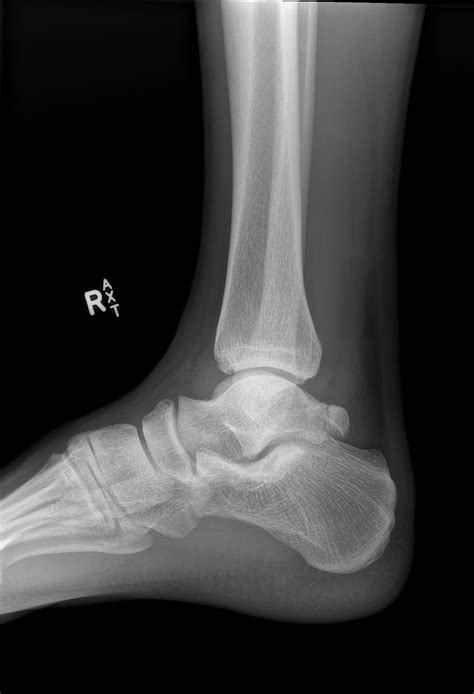

Suffering a shattered talus bone is a serious medical event that can significantly impact your mobility and long-term joint health. The talus is a uniquely shaped bone that sits between your shinbone (tibia), fibula, and heel bone (calcaneus), forming the foundation of your ankle joint. Unlike many other bones in the body, the talus lacks a robust direct blood supply, making it notoriously difficult to heal after a severe fracture. When this bone is shattered—often referred to in medical terms as a comminuted fracture—it requires immediate orthopedic intervention and often complex surgical reconstruction to restore proper alignment and function.

The talus plays a crucial role in transferring your body weight from the leg to the foot. Because it is covered in cartilage on most of its surfaces, it acts as a smooth hinge for ankle movement and allows for side-to-side rotation of the foot. When a shattered talus bone occurs, the integrity of these smooth surfaces is compromised. The complexity of this injury arises not only from the bone breakage but from the potential damage to the surrounding blood vessels and ligaments that are essential for the bone’s viability.

To determine the severity of a shattered talus bone, orthopedic surgeons rely on high-resolution imaging. Standard X-rays provide the initial view, but they are rarely enough to see the full extent of a comminuted fracture. A CT scan is almost always required to map out the fragments in 3D, allowing the surgeon to plan the reconstruction. MRI scans may also be used to evaluate the health of the soft tissues and the status of the blood supply to the bone fragments.